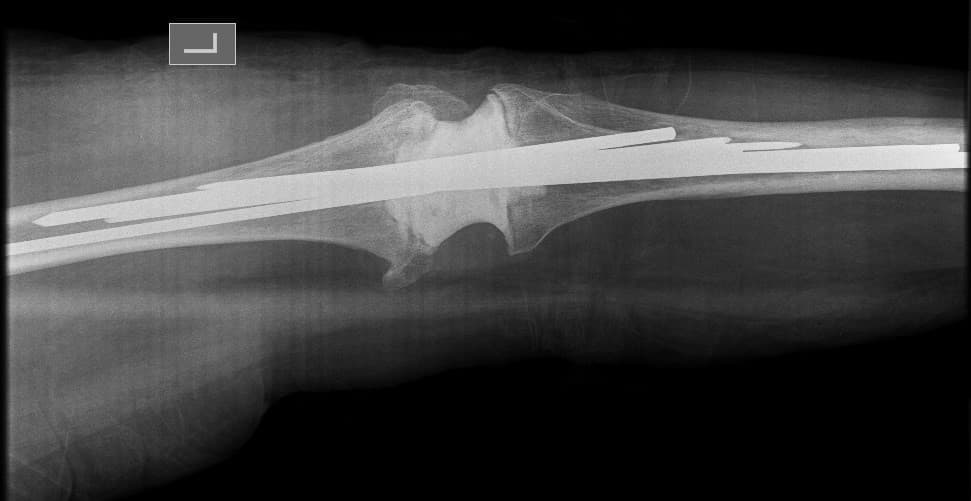

Үе дайрсан ясны анхдагч хавдар, ясны дутмагшлын үед хийгдэх мэс засалimg22Үе дайрсан ясны анхдагч хавдар, ясны дутмагшлын үед хийгдэх мэс засалimg23

Зураг 1. Сэргээн засах мэс заслын өмнөх рентген зураг. Эгц урд, хажуугаас авсан байдал.